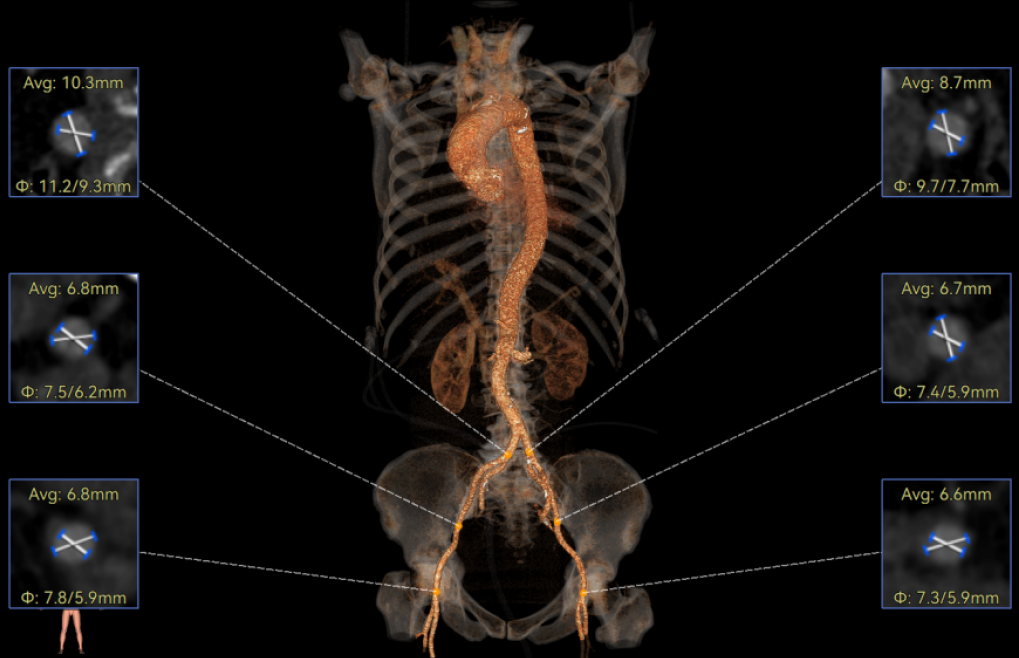

罗建方教授 广东省人民医院(点击查看专家详细简历) 设计本为临床需,耐久守护好芳华:任何医疗产品的设计初衷与最终归宿,都应落在 “临床获益” 这一核心上。尤其在 TAVR 领域,年轻患者预期寿命长,术后瓣膜的长期性能直接关乎其生活质量与生存预后。瓣膜耐久性问题,是落到临床实践中亟待突破的关键课题。传统瓣膜在长期使用中,可能因结构老化、功能退化等问题,难以满足年轻群体数十年的健康需求,二次手术风险也随之攀升。因此,产品设计必须直面这一临床痛点:通过材料革新增强抗钙化性能及生物相容性,以技术突破延长瓣膜有效使用寿命。此次临床应用的预装干瓣Prostyle A®是TAVR领域的革新理念,干瓣预期会为临床提供更耐久性的保障,实现了与临床需求的精准对接,为年轻群体的瓣膜治疗提供更坚实的保障。 李捷教授 广东省人民医院(点击查看专家详细简历) 干瓣技术求革新,性能兼顾护临床:干瓣的技术革新在创新的同时需要和临床实际需求深度耦合,兼顾TAVR术中的核心考量点。临床操作中,瓣膜能否顺利过弓,直接影响手术效率与安全性。Prostyle A®短瓣架设计及第二台阶的柔顺设计,术中操作丝滑;同时,瓣膜植入后的径向支撑力必须平衡得当,才能实现稳定锚定;释放后造影显示:瓣膜形态舒展,轻度瓣周漏,舒张压升高,冠脉开口未受影响;瓣周漏是影响术后效果的关键隐患,双层裙边设计通过多重密封机制降低反流风险,为患者长期获益筑牢防线。这些性能的协同优化,最终目的是让干瓣在临床中真正做到 “好用、耐用、安全用”,为患者预后提升提供坚实支撑。 患者病史 患者因 “活动后气促伴头晕 2 月” 入院。 现病史:2月前无诱因出现活动后气促,休息后缓解,伴头晕,夜间阵发性呼吸困难。超声检查发现:主动脉瓣重度狭窄并重度返流(跨瓣流速 4.3m/s,峰值压差 73mmHg);主动脉 + 冠状动脉 CTA 提示主动脉瓣显著钙化,升主动脉及分支粥样硬化,冠状动脉轻度狭窄(RCA 狭窄 30-40%)。 既往史:高血压病史 15 年,规律服药,血压控制稳定。 术前诊断:非风湿性主动脉瓣狭窄伴关闭不全(重度)、心功能 II 级(NYHA)、高血压病 2 级(高危)、冠状动脉粥样硬化。 术前CT 三叶瓣,瓣叶增厚中度钙化,右无交界钙化粘连,瓣环径25.1mm,LVOT 25.1mm,直筒型结构;窦部空间足够,升主未见增宽,瓣环水平夹角55°;冠脉开口位置佳,无冠脉风险;入路散在钙化、外周双侧入路无明显迂曲,双侧内径可、中分叉,左右侧均能够支持20F 大鞘通过。 造影角度及入路 右窦居中位RAO 5° CAU 26° 左冠切线位LAO 11° CRA 12° 手术策略 右侧股动脉为主入路,左侧为辅助入路;使用20球囊预扩,准备AV26瓣膜,冲洗口朝向3点钟方向送入输送系统性能,初始定位真实瓣环0位释放,最终锚定约瓣下3mm,工作位评估瓣膜稳定性与冠脉情况。 手术过程 根部造影 20mm 球囊预扩无明显腰征 术中使用26号瓣膜,瓣膜释放贴边迅速 80% 工作位观察瓣膜位置良好 释放后造影显示:瓣膜形态舒展,轻度瓣周漏,舒张压由术前30mmHg升为 60mmHg,冠脉开口未受影响。 术后超声:跨瓣流速降至1.6m/s,平均压差降至5 mmHg,心功能显著改善。 Prostyle A®预装干瓣——助力临床最优化解决方案: 1. 抗钙化与耐久性:Micro-EX™专利技术提升瓣膜抗钙化能力,适配患者瓣叶中度钙化的解剖特点,为长期疗效提供保障。 2. 柔顺过弓与精准定位:短瓣架设计 + 远端超滑涂层,确保患者输送系统过弓顺畅;瓣架流入端微直筒设计,让定位贴边更迅速,减少了手术时间; 3. 80% 可回收设计:便于术中调整观察,减少起搏时间,从而减少并发症。 4. 简化手术流程:预装设计缩短操作时间,20F 大鞘兼容外周入路,降低血管损伤风险。